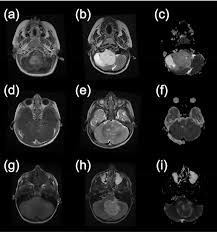

Pediatric Brain Tumor Symptoms Diagnosis And Treatment Doernbecher Children S Hospital Ohsu from www.ohsu.edu Warning signs of a neurological disorder include: Key points about a brain tumor in a child. Problems speaking clearly, swallowing, or walking For example, if a brain tumor is located in the cerebellum at the back of the head, a child may have trouble with movement, walking, balance and coordination. For example, you might tell a child, grandma has to take very strong medicine to get rid of the cancer. If your child has been diagnosed with a brain tumor, memorial sloan kettering is ready to help. A tumor is an abnormal growth of tissue. I promise they won't think you're silly or a hypochondriac!

Medulloblastoma For Parents Nemours Kidshealth from kidshealth.org Brain tumors can grow at any age. The guiding principle should be to tell the truth in a way that children are able to understand and prepare themselves for the changes that will happen in the family. More children than ever are surviving childhood cancer. A ct (computed tomography) scan , mri (magnetic resonance imaging , or possibly both. Wait until you have all of the details. Over your lifetime, the odds of developing a cancerous brain tumor are less than 1%. Help the medical providers taking care of your baby know how your baby has been feeling. How to tell your child.

Opinion Andrew Kaczynski My Baby Daughter Died Of Brain Cancer Here S What We Can Do To Save Other Kids The Washington Post from arc-anglerfish-washpost-prod-washpost.s3.amazonaws.com The types of brain tumors are based on the cell type and location in the brain. Brain tumours are the most common tumours that develop in children. A brain tumor can form in the brain cells (as shown), or it can begin elsewhere and spread to the brain. Problems speaking clearly, swallowing, or walking Boys are affected slightly more often than girls. Your child may have any of the following: Most seizures in children are not caused by brain tumors, but if your child has a seizure, your child's doctor may refer you to a neurologist (a doctor who specializes in brain and nervous system problems) to make sure it wasn't caused by a brain tumor or other serious disease. Headaches, which may become more frequent and more severe feeling of increased pressure in the head unexplained nausea or vomiting